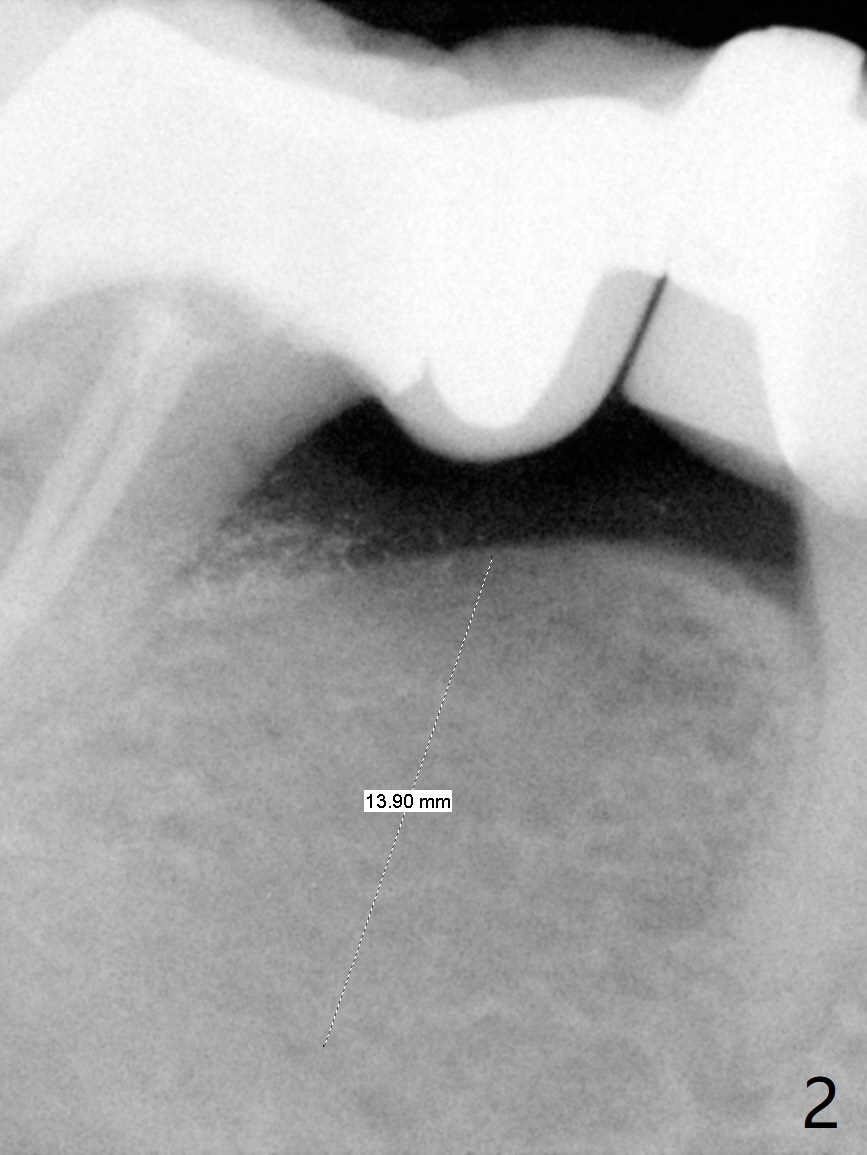

A 60-year-old man has food impaction under the pontic of the lower right FPD (Fig.1-3: #30). The ridge should be thin, since the bone density in the edentulous area is low. The mesiodistal width is also limited. A 1- or 2-piece implant (3.5x8.5 mm, Fig.4 (CT coronal section)) is expected. Use wheel to section the ridge vertically and Rongeur to remove the ridge. Grind the latter for graft. Place a wide abutment to increase the width of the pontic site to reduce food trap.